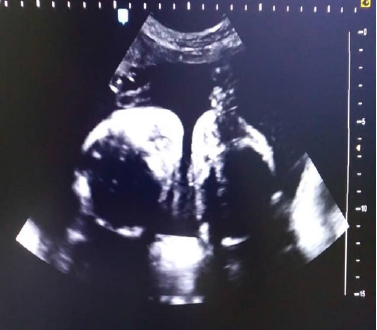

Se trata de paciente femenina de 19 años, sin antecedentes familiares, personales y patológicos conocidos, IV gestas, II cesáreas, I aborto, FUR 18/08/2018, quien acude a especialista en medicina materno-fetal y en vista de hallazgos ecográficos es referida a la Unidad de Perinatología y Medicina Materno-Fetal del Hospital Materno Infantil Dr. José María Vargas, siendo evaluada el 13 de febrero de 2019, donde se realiza estudio ultrasonográfico Perinatal en tiempo real, con transductor convex de 3,5 mHz, ecógrafo marca Esaote, visualizándose estructuras fetales compatibles con dos fetos que correspondían a un embarazo múltiple doble, se identificaron ambos polos cefálicos ubicados en el mismo plano de corte durante la exploración (Figura 1), 4 extremidades superiores, tórax y abdomen de ambos fetos fusionados, corazon único (Figura 2), de difícil evaluacion, impresionando defecto septal ventricular de 4,6 mm (Figura 3), 2 cámaras gástricas (Figura 4), 2 vejigas, sexo femenino, 4 extremidades inferiores, una sola placenta anterior, grado I, grosor 42 mm, con índice de líquido amniótico (ILA) máximo bolsillo vertical (MBV) de 43 mm. Concluyéndose estudio ecográfico con diagnósticos de: Embarazo múltiple doble monocorial monoamniotico (Duplicata completa: siameses toracoonfalopago) de 25 semanas más 4 días por fecha de ultima menstruación con corazon único asociado a posible comunicación interventricular (CIV) sub-aortica.